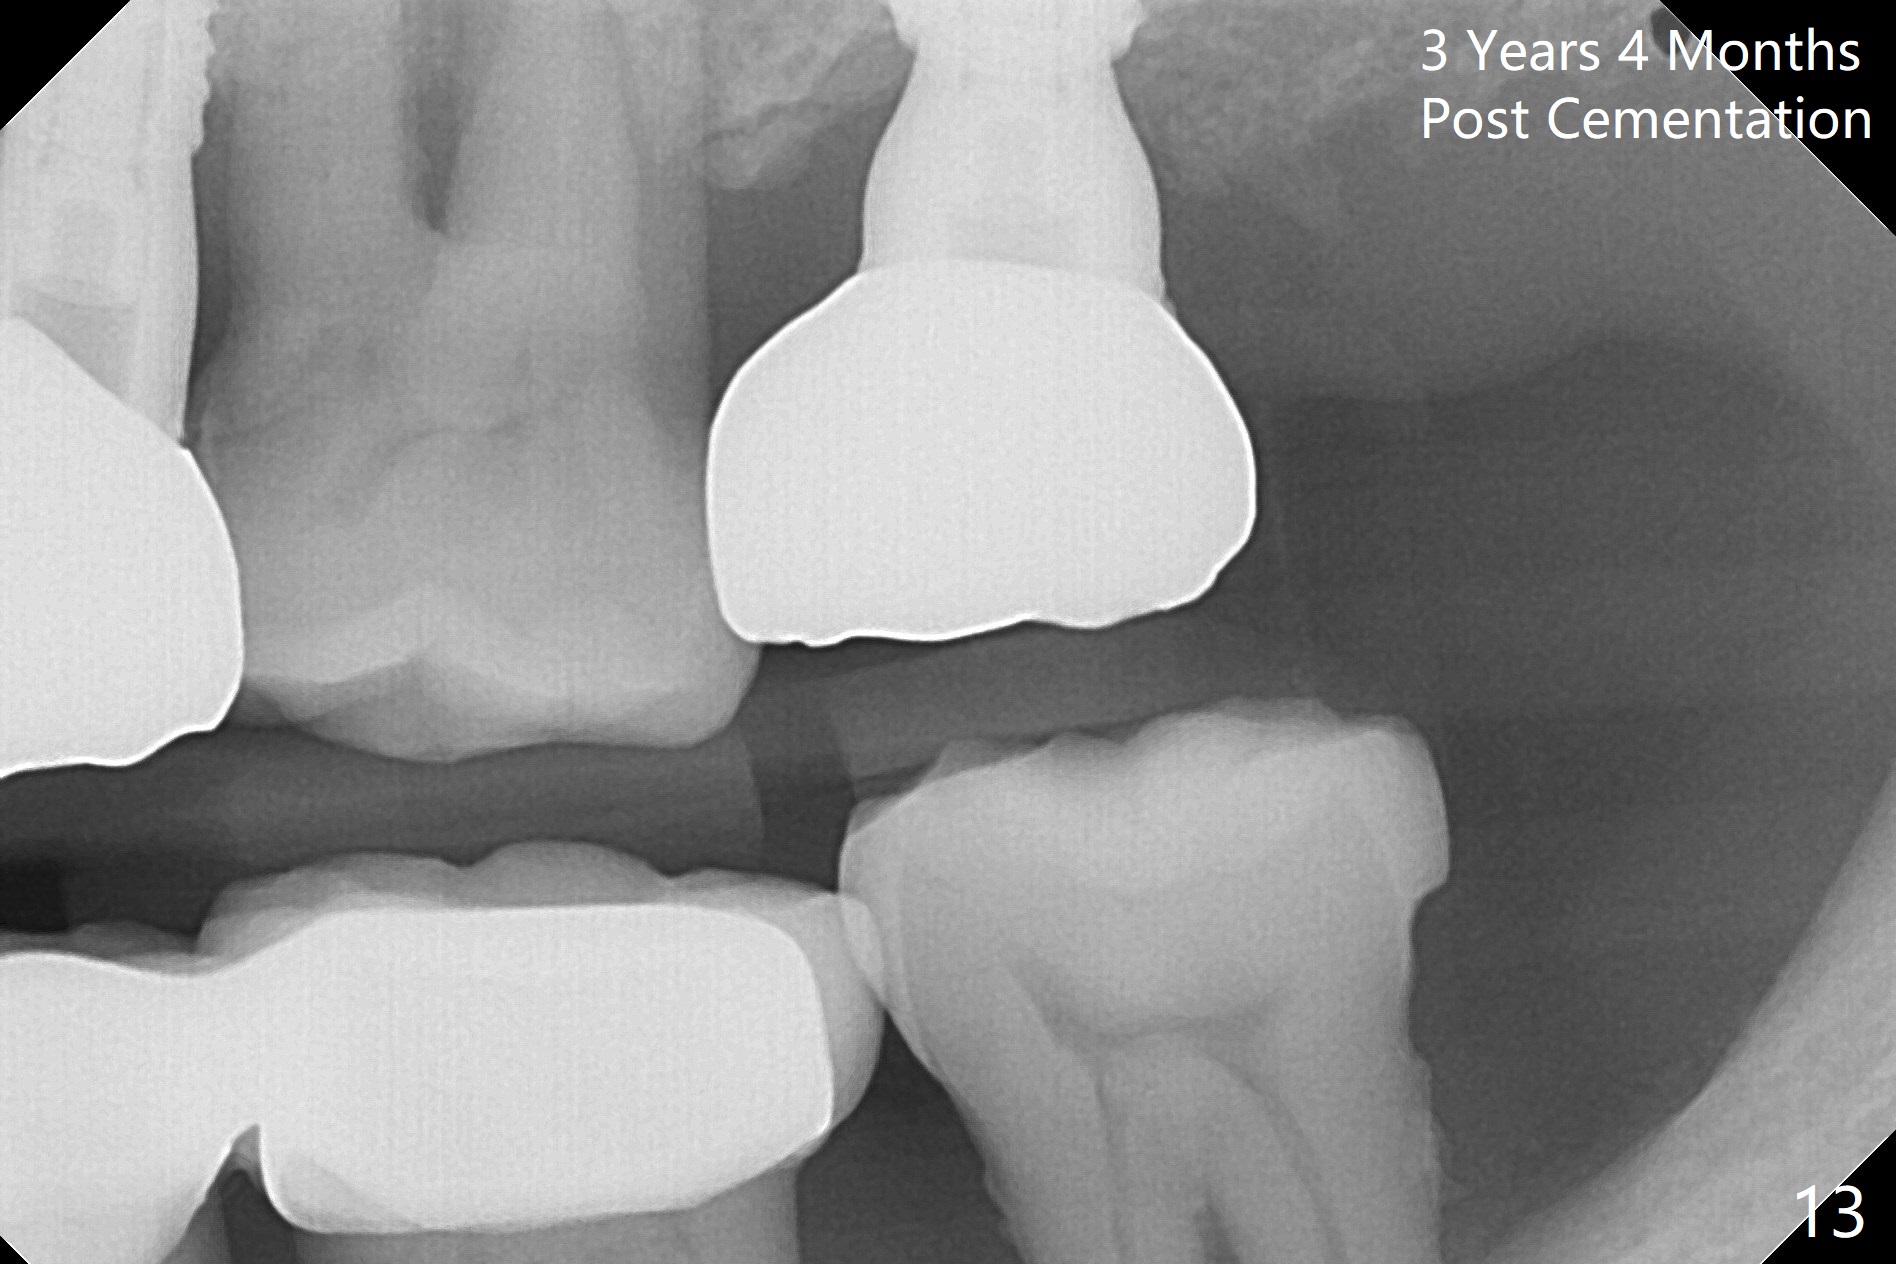

Initial osteotomy depth is 18 mm (Fig.1 green line) with 9 mm in the native bone (red line). The bone density feels to be low. There is at least 2 more mm bone apically (pink line). The depth is increased by 2 mm so that when a 3.8x15 mm implant is placed, there is 10-11 mm implant/bone contact (Fig.2 red line). There is large bony defect (Fig.3 *), which is bone grafted (Fig.4 *). Finally a longer abutment is placed (4.5x5.5(5) in Fig.4 vs. 4.5x4(5) in Fig.2,3). The 5 mm cuff does not look too long buccally (Fig.5) or palatally (Fig.6). To prevent postop buccal gingival overgrowth (2), the buccal margin of an immediate provisional is subgingival (Fig.7-9 *). Bone density between #13 and 14 appears to increase 3 months postop (Fig.10). The implant seems to be equi-crestal (Fig.11 ^). There seems to be more bone growth (i.e., decreasing gap) 6 months postop (Fig.12). Impression is taken. A crown is delivered nearly 7 months postop (08/07/2017). While there is minimal bone loss at #13 and 15 three years and 4 months post cementation, the tooth #14 and 18 are mobile (Fig.13,14).